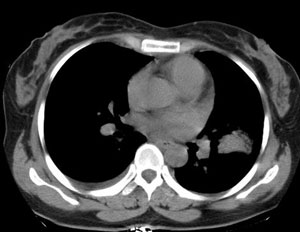

女性,30岁。

病史为胸痛20多天,无畏寒发热,无消瘦,无咳嗽咳痰。总之症状很逍遥。

临床以胸痛待查收住入院。

双肺野可见散在大小不等结节及肿块影,内密度不均匀,边缘部分清,部分欠清,纵隔未见明显肿大淋巴结.右侧胸腔少理积液.结合临床,考虑韦格肉芽肿可能吧,巨淋巴增生,结节病,特殊感染都要考虑.转移瘤临床不象.

本病例特点如下:

1.青年女性,以胸痛20多天就诊,无呼吸道及感染临床症状体征,无原发肿瘤病史;

2.肺ct表现为两肺多发大小不等结节影,大结节位于肺尖部,小结节多位于肺外带胸膜下,大结节内可见支气管充气征,周围可见月晕征(指在结节状或肉芽肿样病灶周围呈环形磨玻璃影),右肺门及腔静脉后可见小淋巴结,右侧胸腔内少量液体。

两肺散在分布大小不等的肿块及结节影,边缘毛糙,有分叶、毛刺,病灶密度不均匀,可见支气管充气相与空泡征。病变大多位于胸膜下,可见胸膜凹陷及胸腔积液。气管腔静脉间可见小结节影。

考虑多发结节型细支气管肺泡癌。